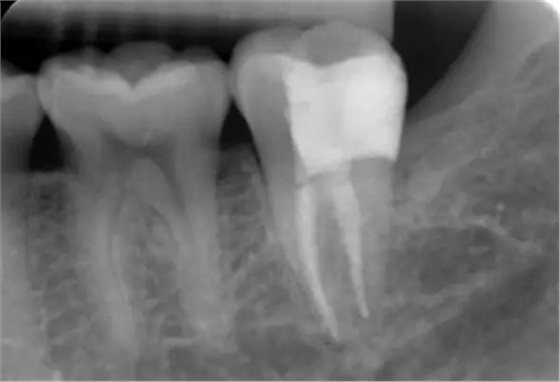

圖11 術(shù)后X線片:37恰填,遠(yuǎn)中鄰面樹脂充填物密合,無懸突。